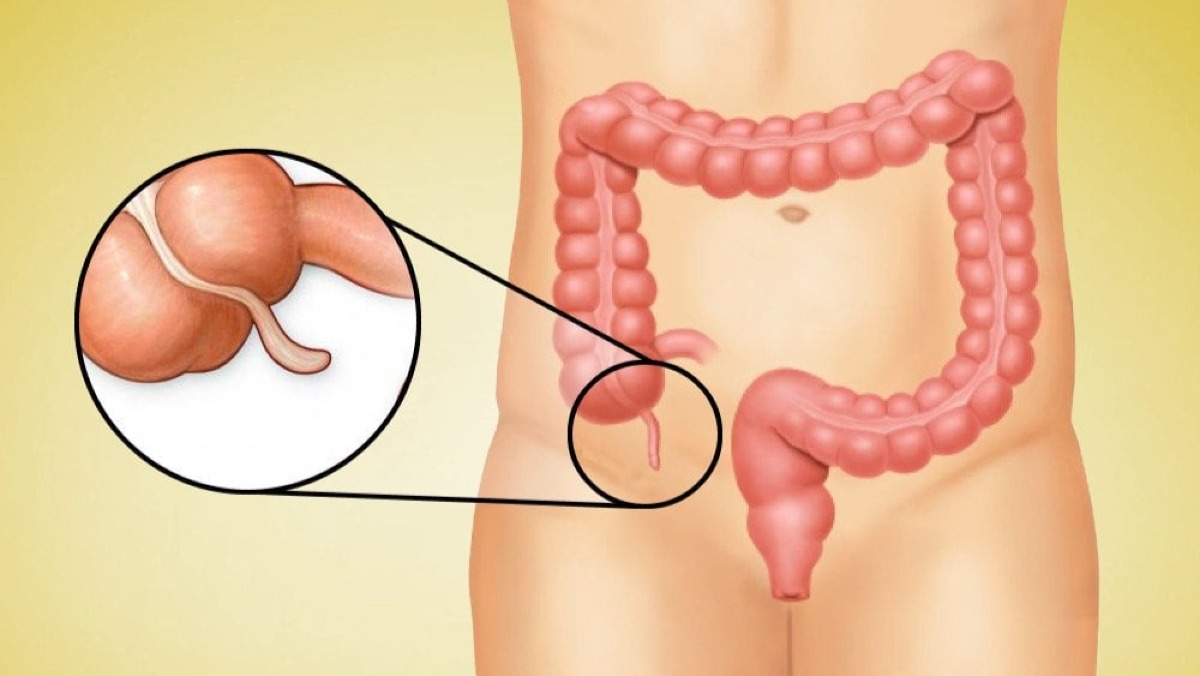

Best Appendix Specialist Doctors in Dhaka, Bangladesh